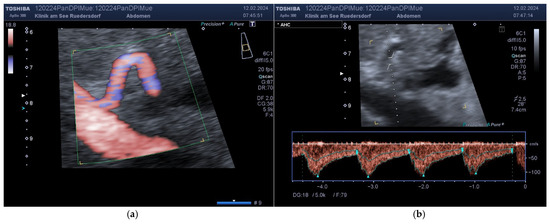

2.3.2. Location of the Probe, Insonation Angle, and Doppler Window